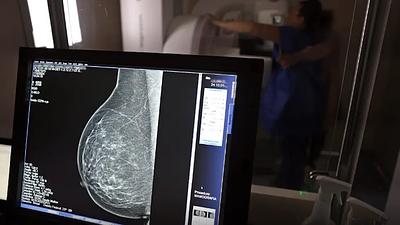

protecaocancermama.jpg

Escassez de mamógrafos dificulta prevenção do câncer de mama

17/10/2025, 12:58

O Brasil tem uma cobertura muito baixa de mamografias: 24%. O ideal recomendado pela Organização Mundial da Saúde é de 70%.